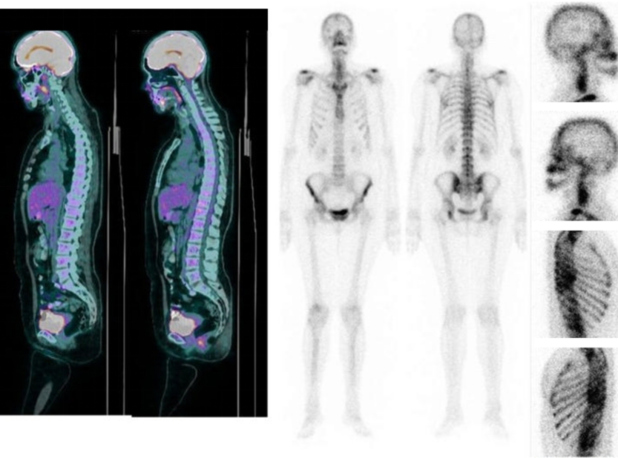

Paciente do sexo feminino, 51 anos, com diagnóstico prévio de carcinoma invasivo de mama, foi submetida a PET/CT FDG-18F, que demonstrou, além da neoplasia primária, lesões osteoblásticas sem expressão metabólica em escápulas, coluna vertebral, arcos costais, ossos pélvicos e fêmur (fig. 1A). Cintilografia óssea (fig. 1B) revelou leve captação inespecífica de 99mTc-MDP compatível com doença articular degenerativa em processos espinhosos de coluna lombar, côndilos femorais laterais e articulações sacroilíacas e coxofemorais.

Tomografia computadorizada de tórax (fig. 2) e ressonância magnética (fig. 3), evidenciaram múltiplas formações nodulares ósseas aleatoriamente distribuídas em arcos costais e corpos vertebrais torácicos e lombares, sem sinais de fraturas patológicas. Biópsia (fig. 4) e estudo imunohistoquimico (fig. 5) foram realizados; a análise histológica revelou medula óssea com celularidade preservada e sem evidência de malignidade. A imunohistoquímica (IHQ) demonstrou expressão para CD3 e CD20 sem expressão de citoqueratina, sugerindo tecido hematopoiético reacional e excluindo neoplasia secundária.

Apesar da localização incomum das lesões, osteopoiquilose foi considerada o principal hipótese diagnóstica devido à ausência de lesões hipermetabólicas em PET/CT(5) e à baixa captação do radiofármaco na cintilografia óssea(6), além da ausência de indícios de malignidade na biópsia e da negatividade da IHQ para biomarcadores tumorais(7).

Seguimento com PET/CT FDG-18F realizado após dois anos evidenciou ausência de progressão das lesões osteoblásticas, o que corrobora com a hipótese de um quadro benigno.

Na paciente aqui relatada, PET/CT FDG-18F revelou lesões em escápulas, coluna vertebral e arcos costais, o que é mais característico de doença metastática. O envolvimento de costelas, clavículas, coluna e crânio na OPQ é raro e menos acentuado. No entanto, isso não impossibilita o diagnóstico de osteopoiquilose, considerando que a apresentação pode ser atípica em idosos devido a mudanças ao longo do tempo(5,7,11). A ausência de dor favorece a hipótese de OPQ, contudo, até 30% dos pacientes com metástase óssea podem não apresentar dor(7). Por ser aceita como uma ferramenta sensível para o diagnóstico de metástases de câncer de mama(7), a cintilografia óssea desempenha um papel crucial na discriminação entre OPQ e doença metastática(1-3,6). Na doença metastática, a cintilografia evidencia "hot spots" de atividade aumentada; na osteopoiquilose, não é evidenciado aumento na captação do radiofármaco(1-3,6). A falta de captação pela cintilografia pode ser explicada pela ausência de sinais de remodelação ativa comumente observada em análise histológica dos focos, refletindo remodelação óssea antiga(11).

Nesta paciente, a cintilografia óssea mostrou leve aumento inespecífico de 99mTc-MDP em processos espinhosos de coluna lombar, articulações sacroilíacas, articulações do quadril e côndilos laterais do fêmur. Esse achado foi compatível com doença degenerativa osteoarticular. Biópsia de região pélvica e imunohistoquímica também foram realizadas e evidenciaram tecido hematopoiético reacional, excluindo neoplasia secundária.